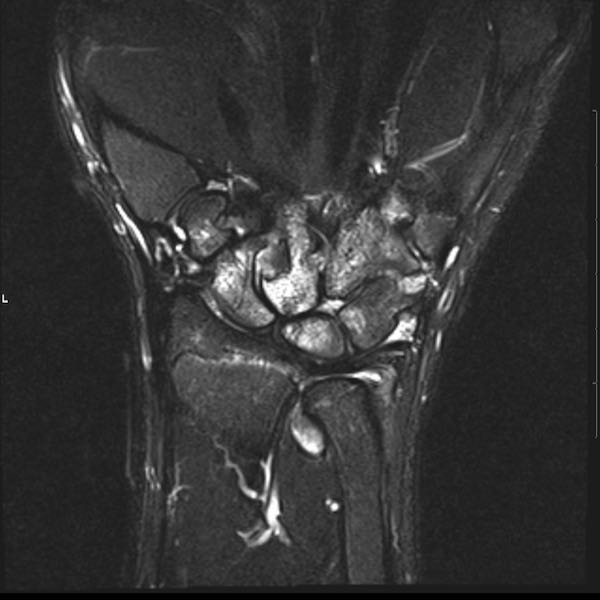

Tiếp tục xem hình ảnh MRI của bệnh nhân này.

Hình ảnh MRI:

Tràn dịch lan tỏa tất cả các khớp cổ tay.

Phù tủy xương lan tỏa tất cả các xương cổ tay.

Bào mòn xương, ví dụ tại xương thuyền, xương đầu và xương móc.

Phá hủy khe khớp và sụn khớp, rõ nhất tại khớp STT và CMC4/5.